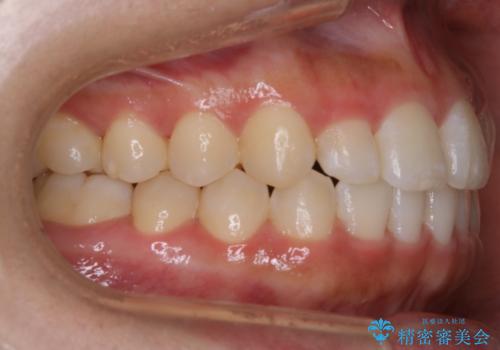

【非抜歯】部分矯正でも治る 前歯の反対咬合

- 前歯にガタつきを主訴にご来院されました。

奥歯の嚙み合わせに問題がほとんどみられなかったため、インビザライン ライトパッケージでの部分矯正を行うこととなりました。

今回のケースでは奥歯の噛み合わせに問題がほぼみられなかったため、前歯の位置のみに焦点を当て部分矯正を行いました。

適応されるケースが限られるものの、適応であった場合の治療期間は全体矯正と比べると格段に短くなり、費用も抑えられます。